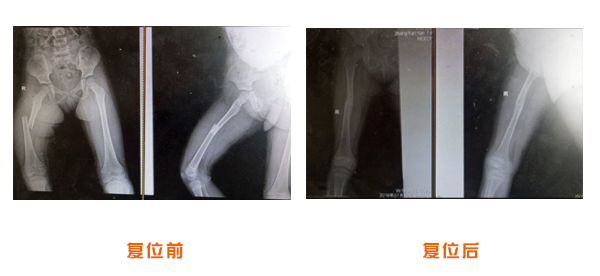

肥城市安駕莊梁氏骨科醫(yī)院是一所以梁氏手法正骨配合膏藥為特色的現(xiàn)代化專(zhuān)科醫(yī)院。

梁氏骨科術(shù)始創(chuàng)于清雍正年間,歷經(jīng)八代,至今已有三百年歷史。據(jù)1929年泰安縣志載“梁瑞圖先生,字增生,號(hào)蓮峰,安駕莊人,精岐黃并發(fā)明接骨,凡跌打車(chē)凡跌打車(chē)軋皮不破而碎骨者......【詳細(xì)】 |